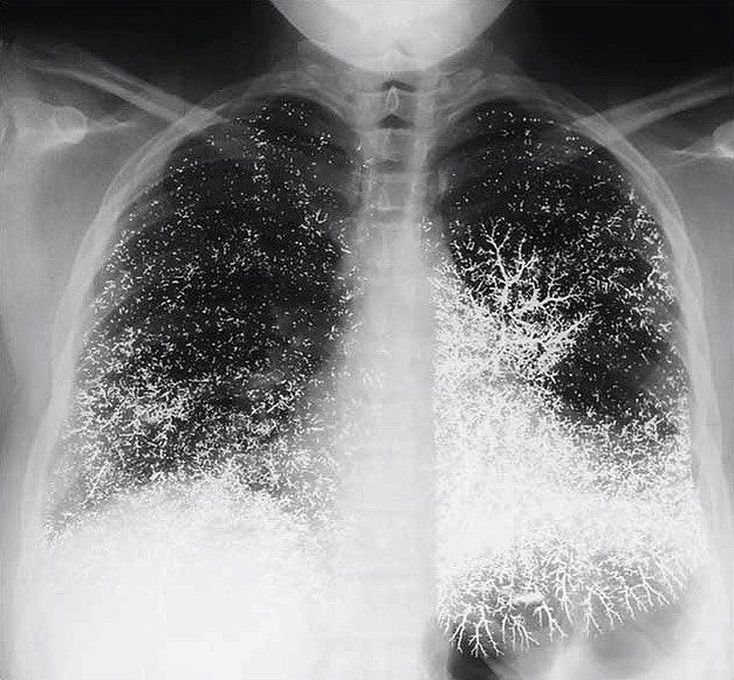

A 21-year-old dental assistant attempted suicide by injecting 10 ml (135 g) of elemental mercury intravenously. She presented to the emergency room with tachypnea, a dry cough, and bloody sputum. A chest radiograph showed that the mercury was distributed in the lungs in a vascular pattern that was more pronounced at the bases. The patient was discharged after one week, with improvement in her pulmonary symptoms. Oral chelation therapy with dimercaprol was given for nine months, until the patient stopped the treatment; the urinary mercury level did not change during this period. At follow-up at 10 months, she was healthy, with none of the renal, gastrointestinal, or neurologic effects that can result from the oxidation of mercury in the blood and consequent exposure of these organ systems. The abnormalities on the chest radiograph were still apparent. Although these abnormalities are striking, the absence of clinical toxicity in this patient illustrates the differences in the acute and chronic effects of exposure to elemental mercury, inorganic mercury (e.g., mercuric chloride), and organic mercury (e.g., dimethylmercury). Inorganic and organic mercury are much more toxic than elemental mercury; for example, a dose of 400 mg of mercury in the form of dimethylmercury is usually lethal.